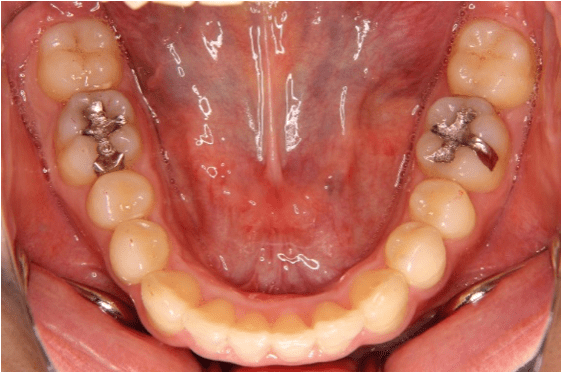

下の前歯を、顎の骨の中で無理なく排列することが出来ました

掲載症例について:

【患者】 20代男性

【主訴】 歯並びのガタガタ

【診断】 叢生

【抜歯の有無】 非抜歯

【治療期間】2年2ヶ月 通院回数18回

【治療内容】親知らずを抜歯した後、マウスピース型カスタムメイド矯正歯科装置(製品名インビザライン 完成物薬機法対象外)を使用して主訴である叢生の改善を行いました。

【費用】88万(税込)

【リスク】矯正歯科装置を付けた後しばらくは違和感、不快感、痛みなどが生じることがあります。

矯正中は矯正歯科装置が歯の表面についているため食物が溜まりやすく、また歯が磨きにくくなるため、虫歯や歯周病が生じるリスクがあります。

歯を動かすことにより歯根が吸収して短くなることや歯肉がやせて下がることがあります。

矯正歯科治療は公的健康保健の適応外の自費治療(自由診療)となります。